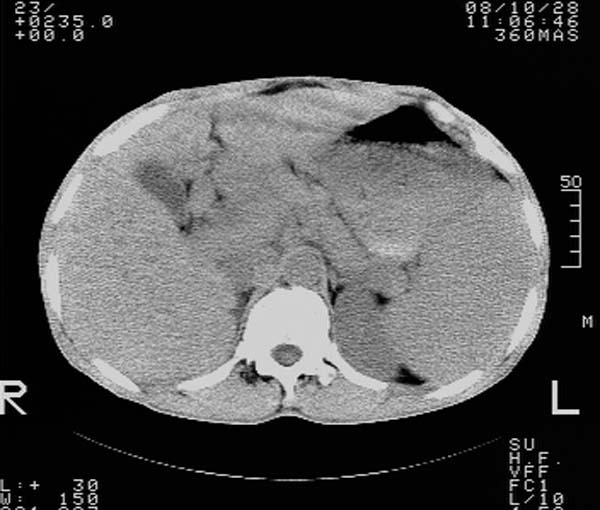

m,65y。半年前发现颈小结节,逐渐增多增大,现双侧耳后、颌下及颈部表浅淋巴肿大。胸片示双肺门增大。外院曾穿刺诊断为淋巴结核。在我科作胸腹部ct,我们觉得外院病检有误。现将图像上传请战友讨论。

纵隔内及腹膜后广泛淋巴结肿大,脾大,肝内似可见低密度影,结合病史半年前发现颈小结节,逐渐增多增大,现双侧耳后、颌下及颈部表浅淋巴肿大。考虑淋巴瘤。

我们也是首先考虑淋巴瘤。只是外院病检报告是结核。让人迷惑。肝左叶多发低密度占位,没增强不好定论。

纵隔,双肺门腹膜后多发淋巴结重大,非融合,肝脾轻度肿大,双肺野弥漫性小结节;考虑淋巴瘤,结节病可能性

纵隔内,双肺门、腋窝及腹膜后多发肿大淋巴结影,肺内小结节影,肝脾体积增大,支持淋巴瘤。肝内多发低密度影,考虑小囊肿。

考虑淋巴瘤肺、肝内转移,脾脏肿大。

纵隔内,双肺门、腹膜后多发肿大淋巴结影及颈部淋巴结肿大,肝脾体积大.结合临床,淋巴瘤可能性大。